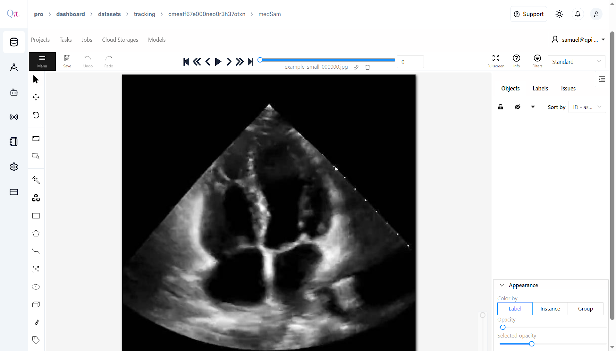

Image 1

Click âAnnotationâ in the toolbar.

- Select âDraw New Polygonâ from the available options.

- On the displayed image, click to place points around the target area, forming a polygon that outlines the region of interest.

- Ensure that each polygon corresponds to the classes you defined during dataset creation, providing accurate visual prompts for segmentation.

- Continue to draw polygon points for the classes you want to annotate manually.